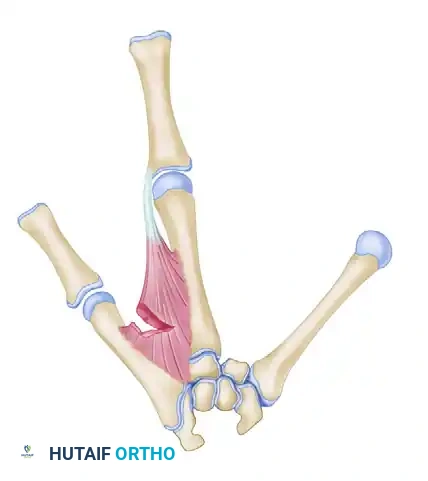

Dorsal view demonstrating the initial skin incisions, flap elevation, and planned wound closure.

- Palmar Flap Elevation: As the incisions pass the metacarpal heads, curve them proximally onto the palm. These incisions should run almost parallel to each other, lying slightly toward the cleft side of the midline of the two fingers.

- Crucial Limit: Do not extend the palmar incisions any farther proximally than a point directly opposite the V-shaped apex of the dorsal incision. This creates the robust palmar flap destined to form the new thumb web.

Palmar view detailing the skin incisions and the elevation of the palmar flap.

- Transpose the large palmar-based cleft flap into the newly opened space between the index finger and the abducted thumb.

Relationship of the thumb adduction contracture release and the palmar flap. If the palmar flap is insufficient to cover the defect, a full-thickness or split-thickness skin graft must be utilized.

- Tension-Free Closure: Never place these flaps under tension. Ischemia will lead to flap necrosis and severe secondary contracture. If the palmar flap does not completely cover the dorsal defect, harvest a split-thickness or full-thickness skin graft to achieve complete, tension-free coverage.